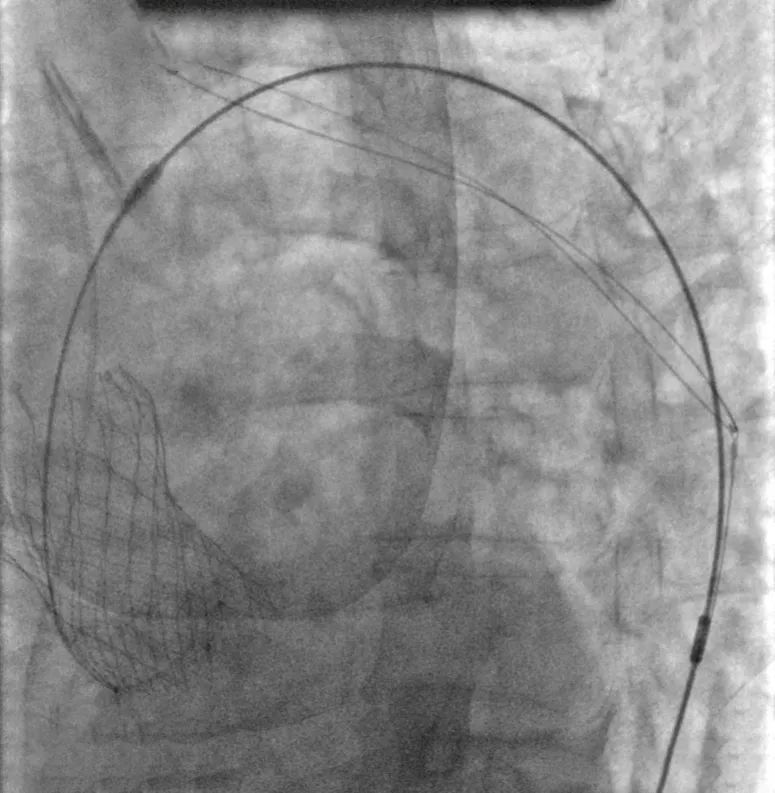

手术开始后,术者用猪尾导管在无名动脉造影辅助下选定TriGUARD3™锚定区,确认释放位置,经由左股动脉送入脑保护装置,使脑保护装置完全覆盖头臂动脉、左颈总动脉、左锁骨下动脉开口。

综合考虑瓣环直径、左室流出道直径、钙化分布等因素,张海波教授在外科王坚刚教授、郑帅教授、麻醉王承彬教授等协助下顺利为患者选择植入一枚VenusA-Valve® L32型号的人工主动脉瓣膜,克服了横位心和扭曲主动脉等难题,介入瓣膜一步到位位置非常满意,血流动力学效果非常好。而且在TriGUARD3™抗栓塞远端脑保护装置的辅助下顺利植入,随后撤出脑保护装置。术中未出现任何并发症,患者术后头部DW-MRI检查显示无体积600mm³ 以上的新发病变,无体积1000mm³以上的新发病变,新发平均病变体积仅为84.37mm3,TriGUARD3™脑保护装置有效阻挡整个TAVR手术过程中栓塞物质进入脑部,从而避免新发大体积病灶产生。术后患者恢复良好,为此次手术圆满画上句号。

脑保护装置与VenusA-Valve完全释放